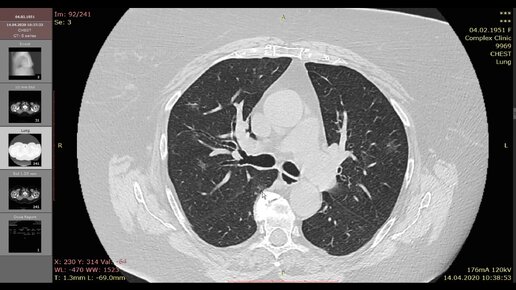

Коронавирус на КТ легких (признаки COVID 19)